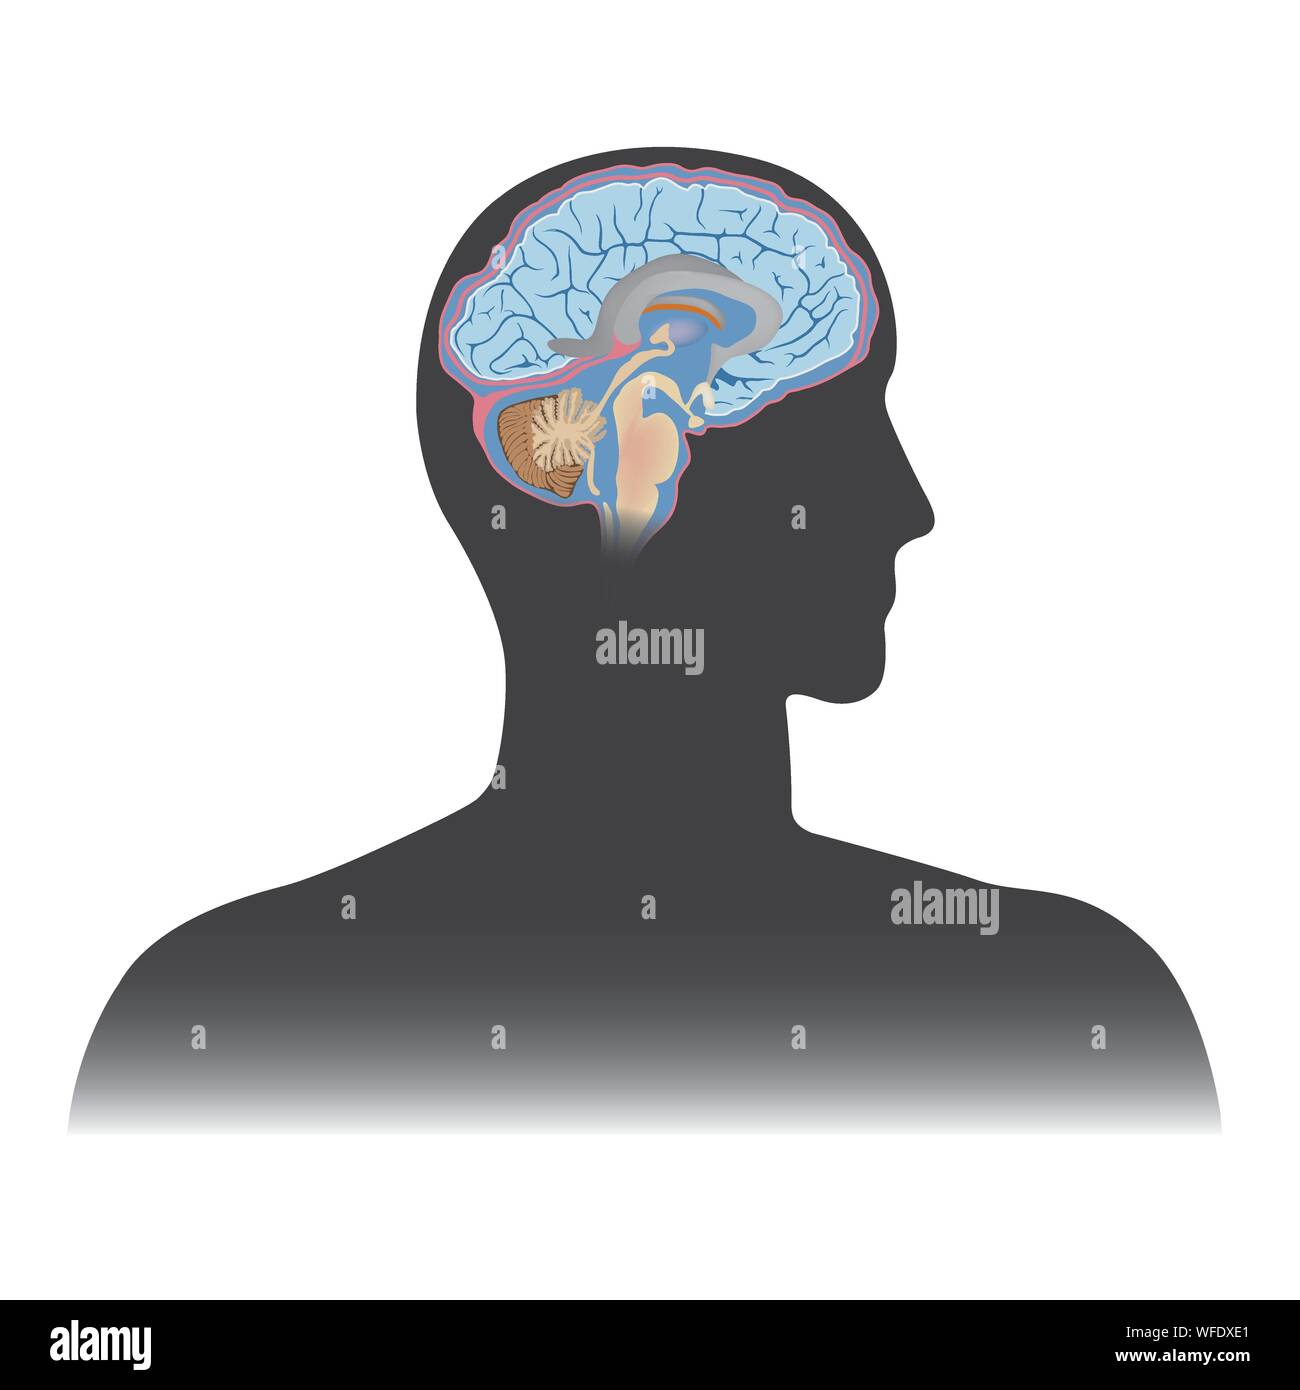

RF2EAHBMJ–Illustrazione isolata vettoriale dei componenti cerebrali nella testa dell'uomo. Anatomia dettagliata del cervello umano.

RFRPYAGD–Struttura del cervello umano. Testa umana con all'interno del cervello. Cervello umano parti principali. Illustrazione Vettoriale.

RF2PPWR9E–Cervello umano con parte del sistema limbico e corteccia cerebrale, nucleo suprachiasmatico, chiasmo ottico, Ipotalamo, E Pineal Gland